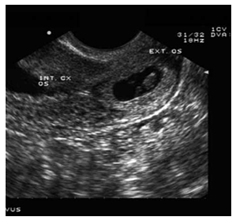

Mulher de 26 anos dá entrada na emergência referindo dor abdominal súbita de forte intensidade há 40 minutos, acompanhada de sudorese, palidez cutaneomucosa, tontura e mal estar geral. Refere atraso menstrual há cerca de 8 semanas. Sinais vitais: PA: 90/55 mmHg; FC: 132 bpm; FR: 26 mrpm. Exame físico: dor à palpação abdominal difusamente, DB +, toque vaginal com abaulamento dos fundos de saco. Sinal de Proust positivo. Solicitado ultrassom (imagem demonstrada a seguir).

Enunciado 4925948-1

(Tissiani, J.; Martins, W . P. et al. Experts in Ultrasound Reviews and Perspectives 1(2):100-106 DOI:10.4281/eurp.2009.02.07)

A conduta a ser realizada com a paciente deverá ser: